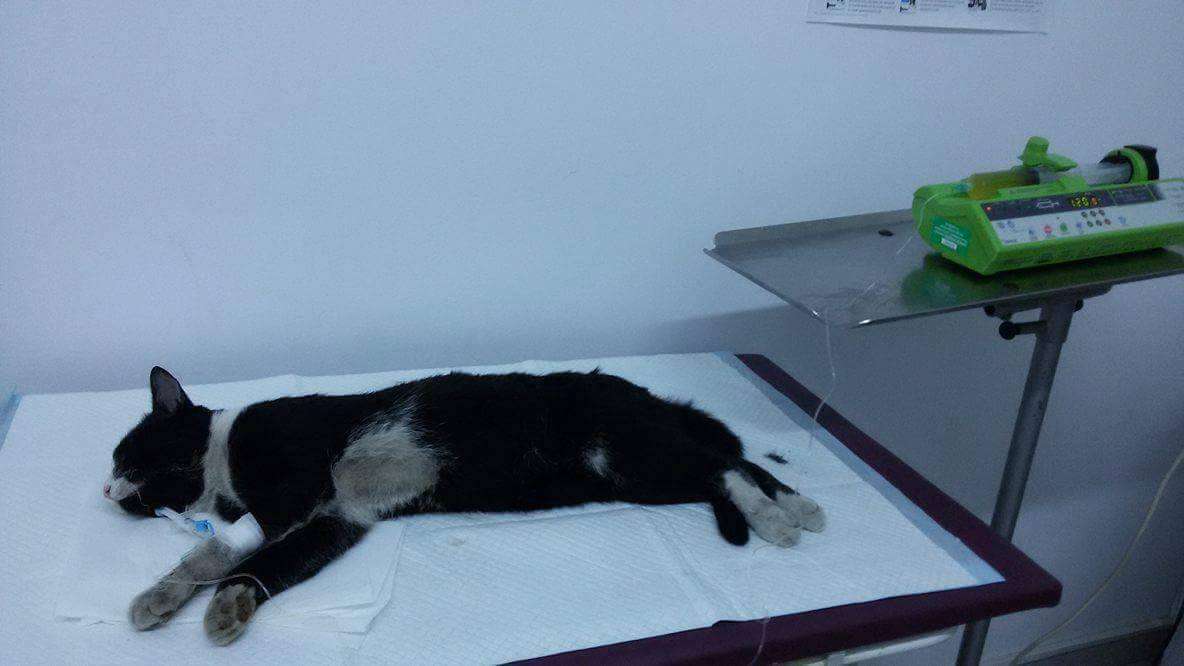

She was wondering on the streets looking for a human with a soul to love her and in return she’ll offer all her love and loyalty. In this way she found a bastard homeless who beaten her till broken her jaw, she has legs problems and who knows what we’ll still discover during investigations but she, kind and loyal soul, was standing and enduring all this treatment without leaving his side unless she was going to look for food when she was hungry. In this way it was succeeded to capture her and now she’s safe, at the clinic, where she’ll receive all the necessary care till she’ll be well in order to take her in our sanctuary from where she’ll leave only to a family that will truly love her.

Update Sanny

Sanny has had a successful operation to repair her jaw- all went well. Now she has a long recovery ahead of her.Now is a time for patience and love as we feed her soft food slowly. In the long run, I hope all will go well for Sanny.

We have to let Sanny recover from her jaw operation to address the other health issues she faces such as her legs, etc.

I know that step by step with love and patience, Sanny will become a healthy girl.